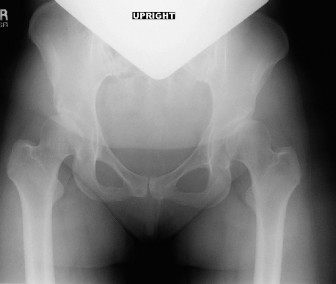

A 52-year-old postmenopausal female presents with progressive hip pain. She points to the pain in “C-clamp” d…